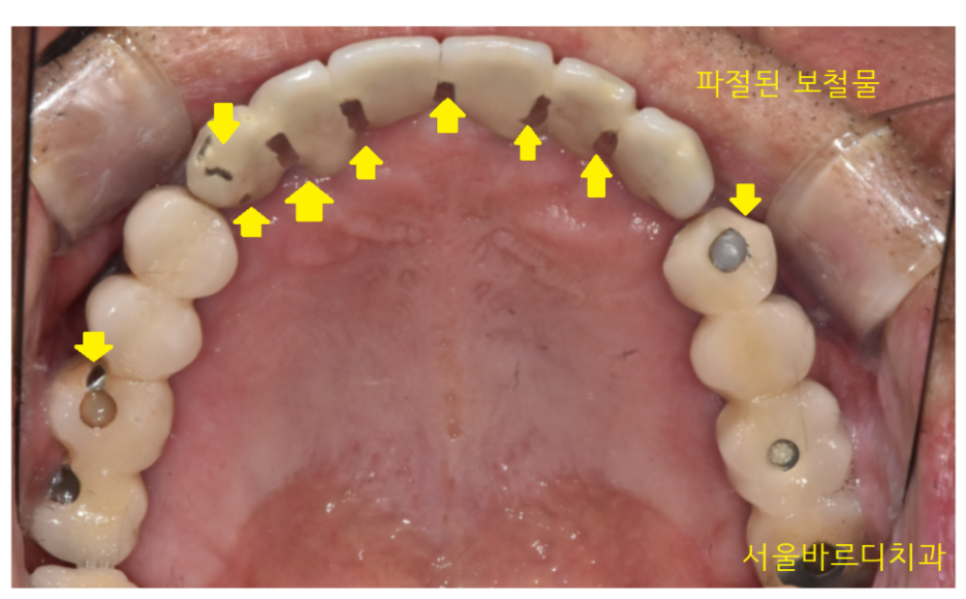

세번째, 딱딱하고, 질긴 음식 피하기

23.04.14

오징어, 젤리 , 얼음, 육포 등등

딱딱하고 질긴 음식은 임플란트에 무리한 힘을 유발합니다.

보철이 깨져나갈 수도 있고

장기적으로 임플란트에 부정적인 영향을 주기 때문이죠ㅠㅠ

물론.. 일반 치아에도 안좋습니다

씹고 싶은 마음은 잘 알지만

치아를 위해서라도 잘게 잘라서 먹는 습관이 좋아요~